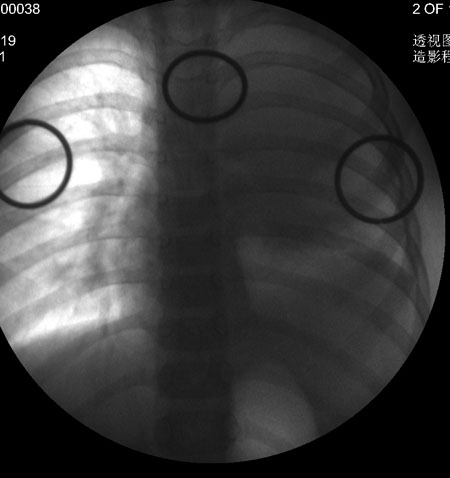

透视采集图像!

此病人是我接手的,发热、咳嗽来做胸透,透视见左侧肺野大部密实,纵隔、心影明显左移,呼吸示纵隔摆动、膈肌矛盾运动(透视下采集了几幅图片),左肺动度明显减弱。询问病人家长,没有吃花生米等呛咳史。由于其影像特征明显,当时诊断:考虑左侧支气管异物并阻塞性肺不张、肺炎。